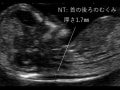

ケミカルアボーション(化学的流産)

これだけ早く妊娠検査が陽性に出るようになると、早めに病産院を受診する方も増え、超音波検査をしても、子宮に胎のう(赤ちゃんが入っている袋)がまだ見えてこないことが多くなりました。通常、その後に胎のうが見えてくるのですが、子宮外妊娠や、ケミカルアボーション (化学的流産)も考慮しなければならず、1~2週間様子を見て、正常な妊娠かどうかを確認する必要がでてきます。◆ケミカルアボーション(化学的流産)

尿中のhCG測定で妊娠反応を認めたものの、胎のうが確認される前に月経様出血へ至ったもの。着床はしたものの、極初期に妊卵の発育がとまったもので、医学的には流産とはいいません。詳しくは「化学的流産(ケミカル・アボーション)とは」も参考にして下さい。ケミカルアボーションになる程度のhCGでは、かつての検査薬は反応しなかったため、いつもと少し違った生理?ととらえられていましたが、検査薬の感度が上がることで生まれてきた概念で、新たたな悲しみをもたらすことになりました。